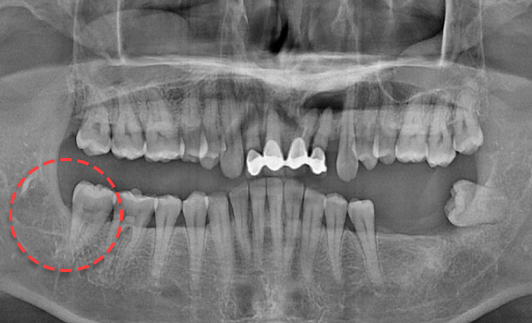

왼쪽 하악 매복 사랑니 발치 Before X-Ray

치료시작일

2020.05.24

AFTER

왼쪽 하악 매복 사랑니 발치 After X-Ray

치료종료일

2020.06.29

왼쪽 하악 매복 사랑니 발치